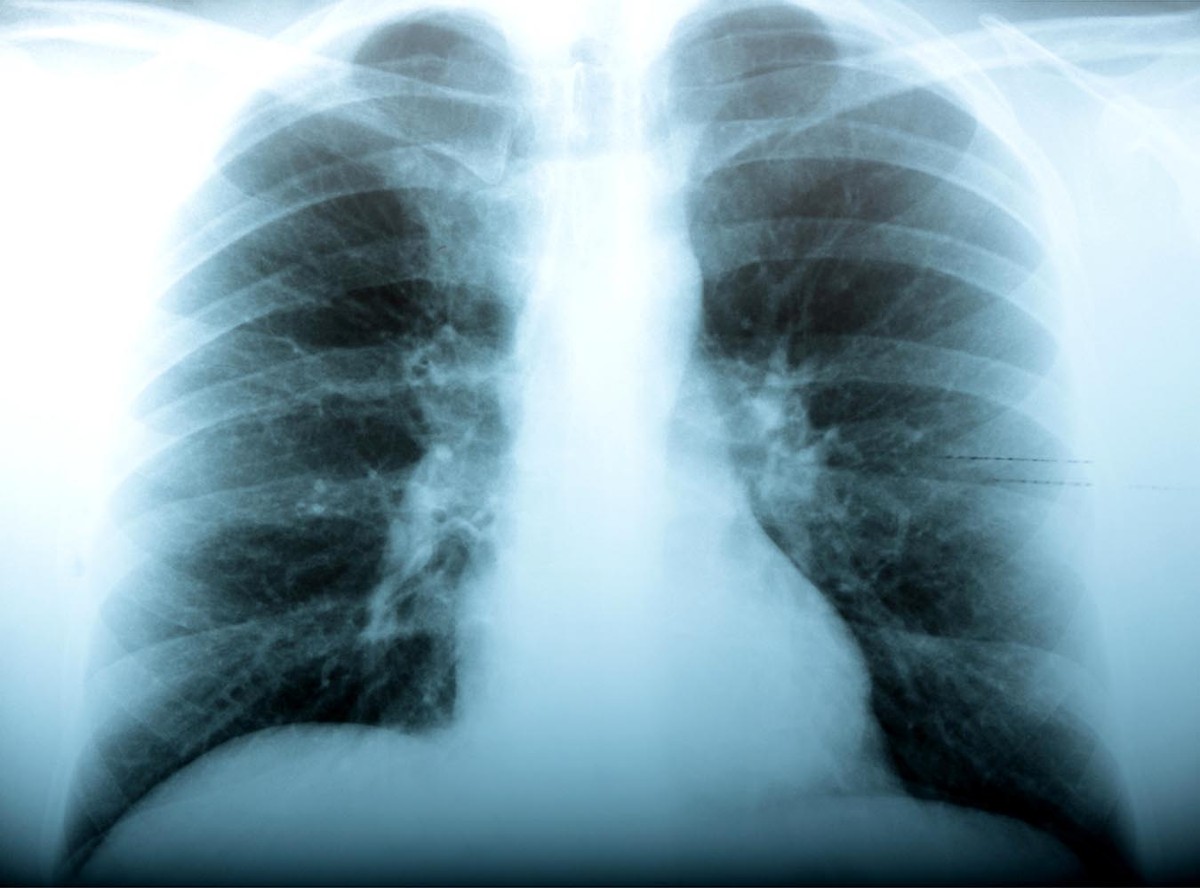

Czy najgorsze prognozy stają się faktem? Brytyjscy naukowcy sprawdzają, czy szalejący na Ukrainie szczep wirusa A/H1N1, który zabił tam niemal 200 osób, nie jest groźną mutacją. Ukraińscy lekarze, którzy przeprowadzali sekcje zwłok ofiar, mówią, że miały one czarne, jakby spalone, płuca.

Zdaniem niektórych lekarzy, grypa na Ukrainie zaczyna przypominać objawami słynną morderczą "hiszpankę", która po I wojnie światowej zabiła miliony ludzi na całym świecie. O wstrząsających spustoszeniach, jakie wirus sieje w organiźmie, opowiedział jeden z lekarzy z zachodniej Ukrainy.

"Przeprowadzaliśmy sekcje zwłok dwóch ofiar i odkryliśmy, że ich płuca były czarne jak węgiel. Wyglądały jak spalone. To było przerażające" - relacjonował.